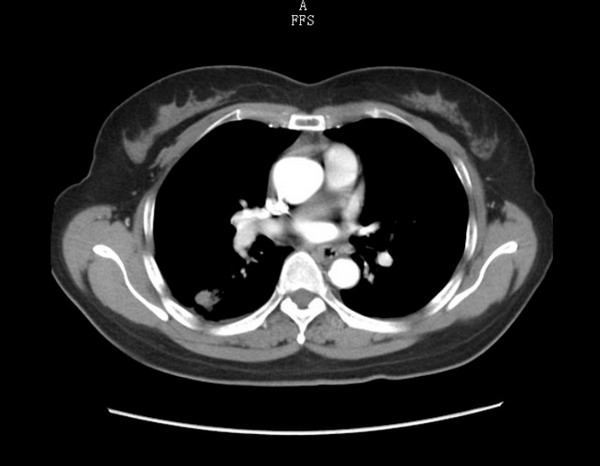

CT示右肺下叶结节(纵膈窗)